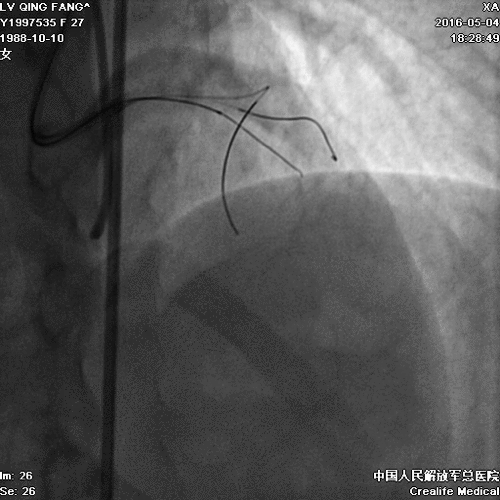

• PCI难点:需要同时开通前降支和回旋支;

• 手术难度大、前降支和回旋支闭塞,前降支闭塞段长,开通一支可能性大,同时开通难度大。

PCI